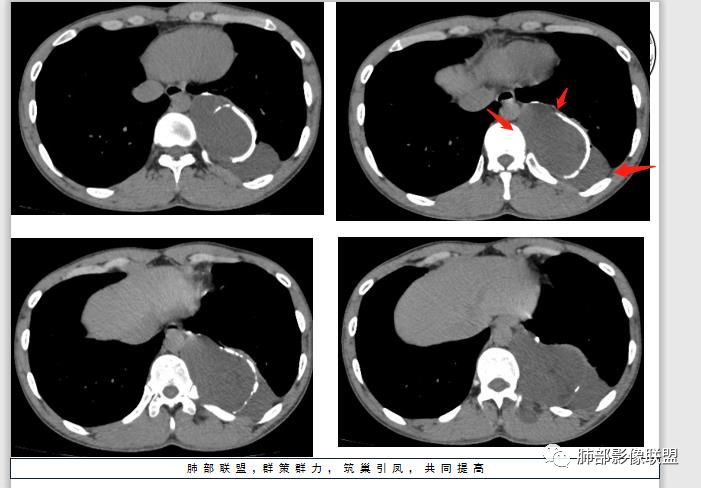

4.冬眠瘤为含有棕色脂肪成分的脂肪瘤,又称为棕色脂肪瘤,因类似冬眠动物的冬眠腺而得名。良性,生长缓慢,好发年龄30-40岁,男性稍多。血管丰富有时会触及局部皮温相对高。

脂肪瘤临床触诊偏柔软较有特点,CT影像脂肪组织成分是最重要的依据之一。

本例无论是临床还是影像都可能怀疑到脂肪类肿瘤,但落实到冬眠瘤难度颇大。

(棕色脂肪细胞比黄色脂肪内含有大量线粒体,且血供丰富,所以氧化充分且产热较多;寒冷可以刺激棕色脂肪细胞分界、氧化从而产生更多的热量,所以这种肿瘤体表上摸上去温度比较高。)